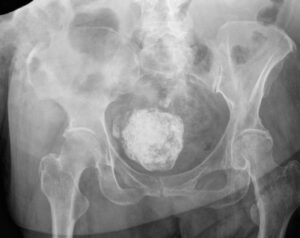

This x-ray reveals a fairly large uterine fibroid

Uterine fibroids are non-cancerous tumors that develop in the wall of your uterus. Fibroids can grow alone or in clusters; they vary in size, from microscopically small to rare cases where they grow to the size of fully-developed fetus.